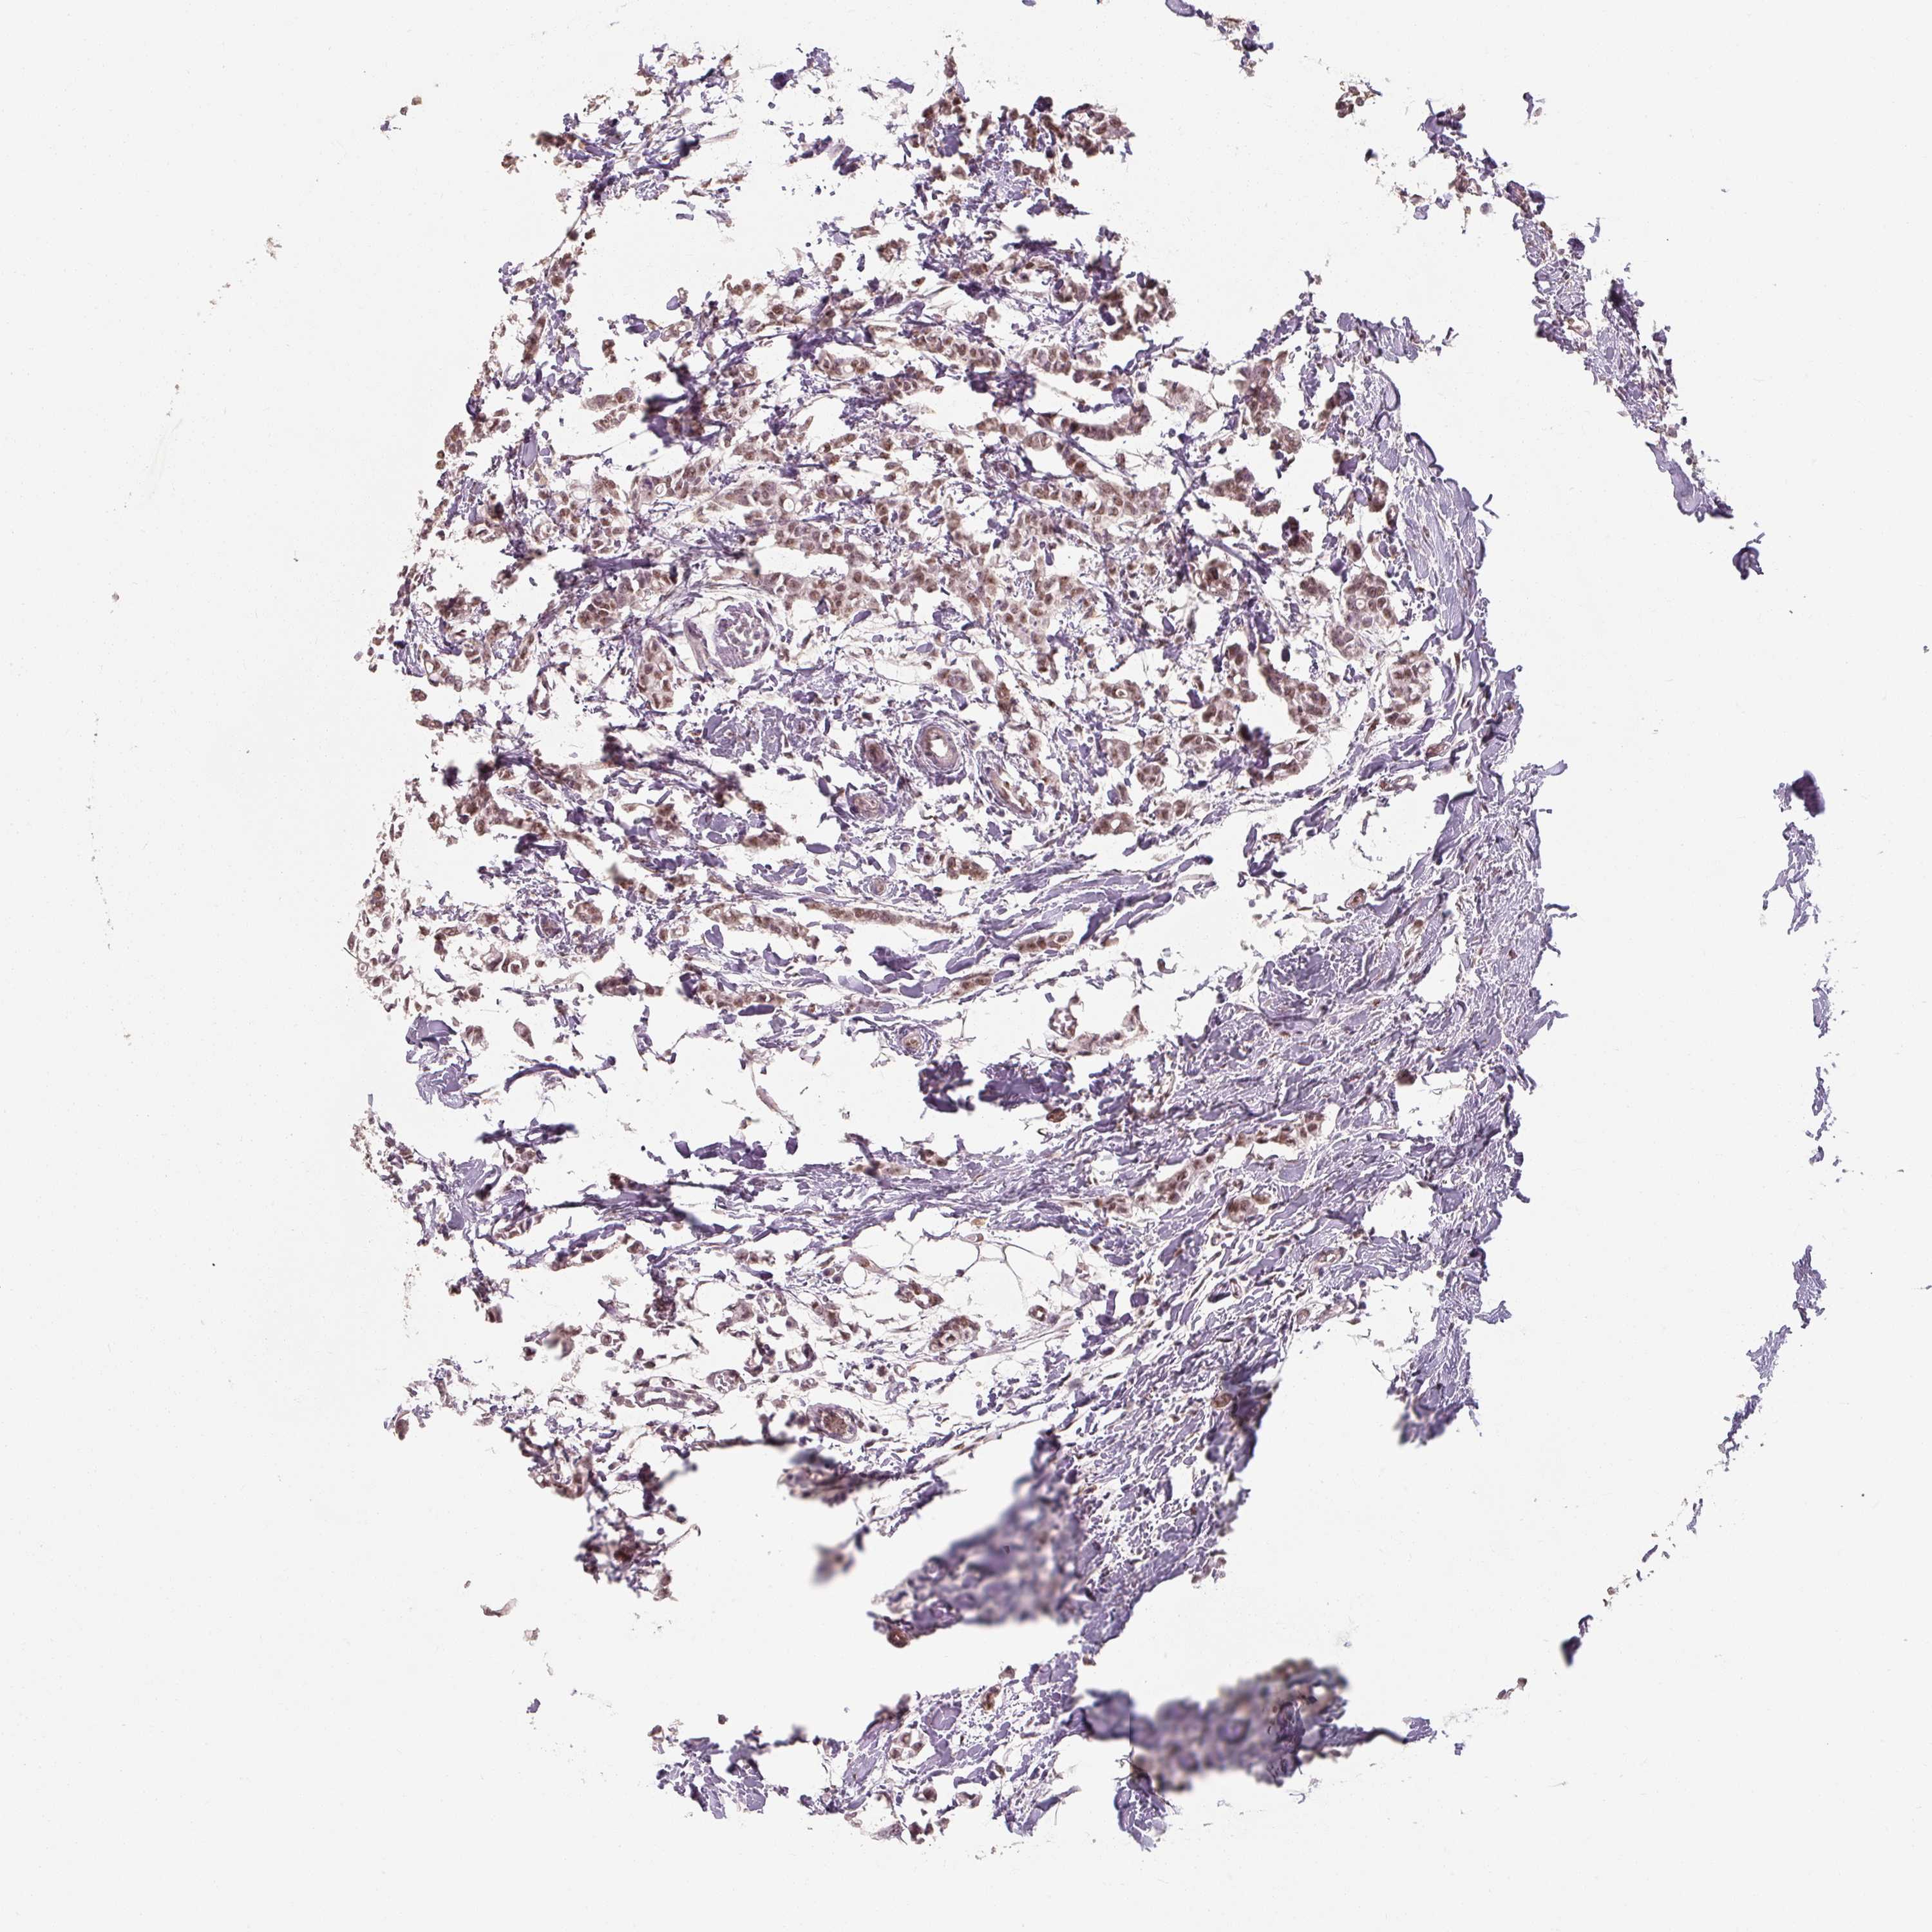

BREAST CANCER - Protein expressioni

A mouse-over function shows sample information and annotation data. Click on an image to view it in a full screen mode. Samples can be filtered based on level of antibody staining by selecting one or several of the following categories: high, medium, low and not detected. The assay and annotation is described here.

Note that samples used for immunohistochemistry by the Human Protein Atlas do not correspond to samples in the TCGA dataset.

Antibody stainingi

Antibody staining in the annotated cell types in the current human tissue is reported as not detected, low, medium, or high, based on conventional immunohistochemistry profiling in selected tissues. This score is based on the combination of the staining intensity and fraction of stained cells.

Each image is clickable and will lead to virtual microscopy that enables deeper exploration of all samples and also displays staining intensity scores, fraction scores and subcellular localization as well as patient and tissue information for each sample.

Antibody HPA053653

Staining

High

Medium

Low

Not detected

Intensity

Strong

Moderate

Weak

Negative

Quantity

>75%

75%-25%

<25%

None

Location

Nuclear

Cytoplasmic/membranous

Cytoplasmic/membranous,nuclear

Duct carcinoma

Lobular carcinoma